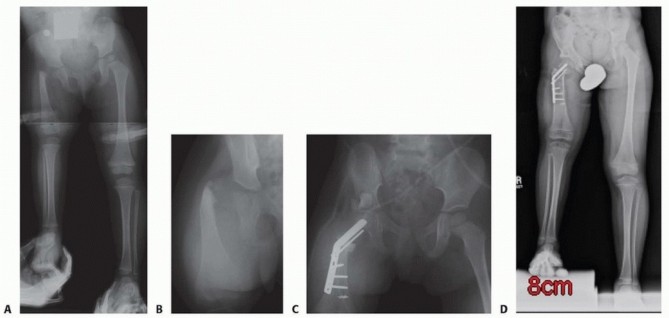

Prosthetic reconstruction surgery is recommended for most type 3 CFD due to the extensive deficiency present. This is especially the case for type 3b because there is a stiff knee joint (<45 degrees of motion). Although type 3a can be converted to type 2b, the treatment would consist of four or more lengthenings. Rotationplasty is recommended for most type 3a because it provides a more predictable functional result than does lengthening ( FIG 7 ).

Saghieh and associates14 studied our first 79 consecutive patients with Paley type 1 CFD. The patients underwent 99 femoral lengthenings between January 1988 and December 2000. Medical charts and radiographs were retrospectively reviewed. Fifty-nine patients (73 lengthenings) had Paley type 1a and 20 patients (26 lengthenings) had Paley type 1b CFD. Forty-six (58%) were female and 33 (42%) were male patients. The mean patient age was 12.3 years (age range, 1.5 to 62.3 years). The lengthenings were divided into three age groups: toddler (younger than 6 years), juvenile (between 6 years and skeletal maturity), and adult (skeletally mature). Because 19 patients each underwent more than 1 lengthening (18 underwent 2 lengthenings and 1 underwent 3 lengthenings), each lengthening was evaluated independently as a separate lengthening and studied for its own results and complications.

The average discrepancy in femoral length was 9.1 cm (range, 1.2 to 22.1 cm) preoperatively and 4.1 cm (range, 14.7 to 2.3 cm) postoperatively. The mean distraction gap was 5.8 cm (range, 2.4 to 12.0 cm). The average duration of treatment with external fixation was 5.9 months (range, 2 to 15.9 months) with an external fixation time index of 1.07 months per centimeter (range, 0.49 to 2.38 months per centimeter). The result score was excellent in 61 (61.6%) lengthenings, good in 29 (29.3%), fair in 7 (7.1%), and poor in 2

(2%).

Excellent and good results were achieved in 91% of patients. No significant differences in most of the studied parameters, including result score, were observed among the different groups. The two younger groups experienced a higher incidence of fracture (no prophylactic rodding was used in this group). The adult group experienced a higher incidence of delayed union and joint stiffness. However, the overall complication rates were similar among the three groups. We prefer to begin lengthening at an early age so that additional needed lengthenings can be spaced in time.